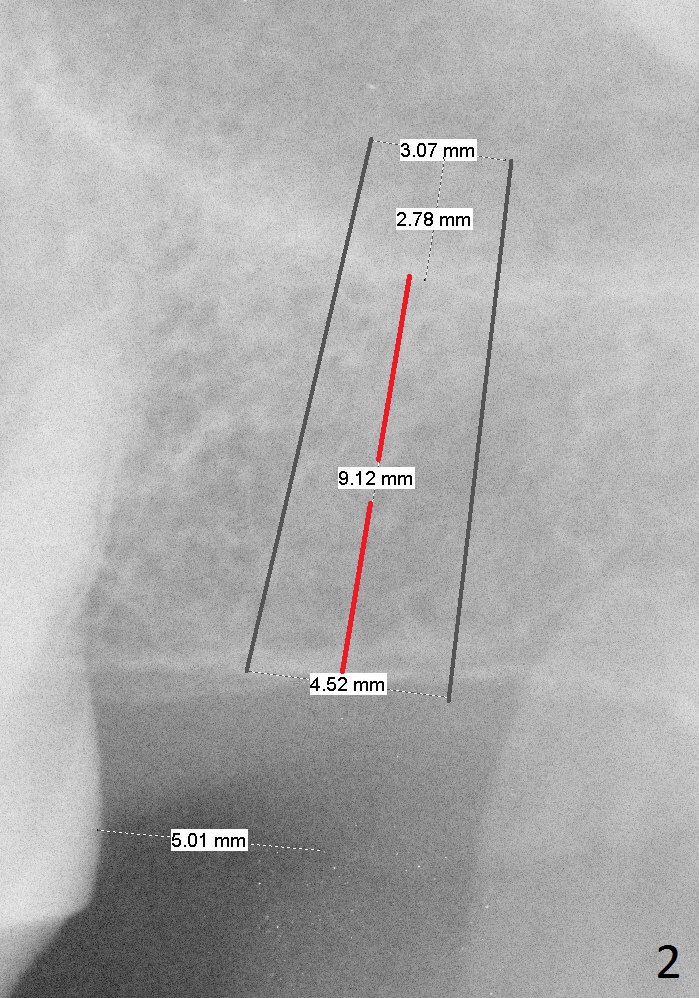

A 65-year-old woman will return to have an implant placed at the site of #15 a few years after that at #19 (Fig.1). Clinically there is limited vertical clearance and the ridge is narrow. These 2 problems will be handled with placement of the implant deep and use of bone expanders, respectively. To protect the sinus membrane, the initial osteotomy depth is going to be 10 mm (9-1+2 mm, Fig.2) with an increase of 1 mm in depth with each of the bone expanders. Take PA with the initial drill. Prepare IBS implant and the one used last time for the patient, including healing and restorative abutments.